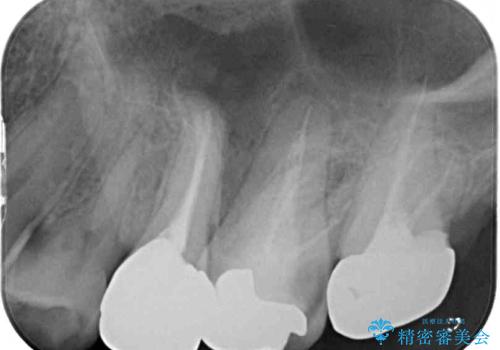

治療後すぐに痛みが引き、治療後半年が経過した際のレントゲン写真では、排膿の元となっていた、歯根先端の病変の消失が認められました。